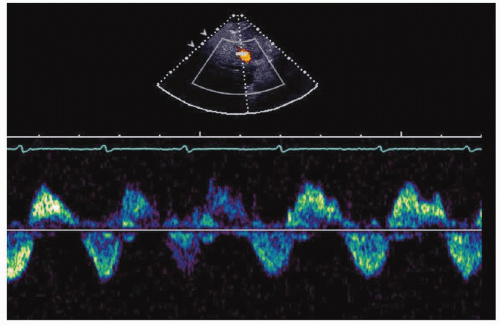

15. Which of the following is most compatible with the hepatic venous flow in Figure 28-1?

View Answer

15. Answer: C. The hepatic venous flow shows holosystolic reversal compatible with severe TR, as in the setting of infective endocarditis of the tricuspid valve. A patient with controlled blood pressure has normal RA pressure and predominant forward systolic flow, not systolic reversal. In the setting of RV infarction and acute inferior wall MI, RV filling pressures are increased and there is predominant forward diastolic flow in the hepatic veins. Systolic flow is reduced, but not reversed in atrial fibrillation.